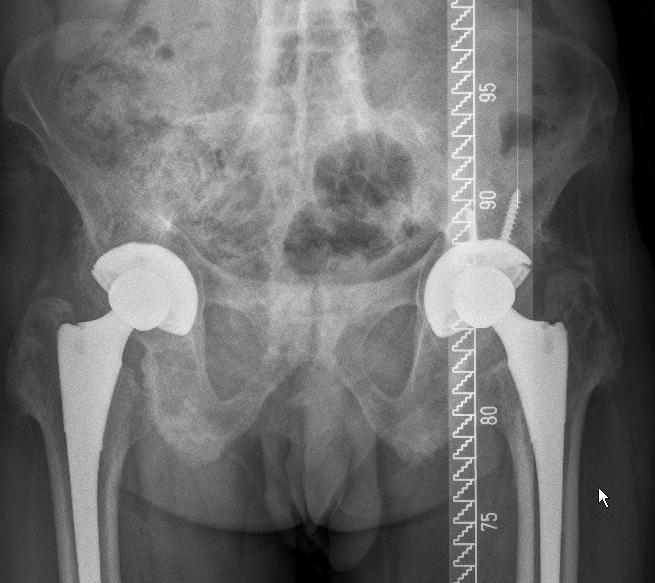

第三期:强直性脊柱炎。

除了一般治疗之外,通常都需要一些药物的干预。药物的干预包括哪些呢?常见的有抗炎镇痛药,有时候可能会用到激素或者是一些生物制剂,得根据病人不同的病情和病程的发展来选择这些药物的治疗。当疾病影响到了脊柱和关节,引起关节强直,关节功能丧失了的时候,那医生有没有别的办法?当然,医生可以通过外科手术的办法,比如说人工关节置换术来改变关节的强直畸形,让病变的关节可以恢复到正常的活动度,让他恢复行走,回归生活和工作岗位,提高生活质量。